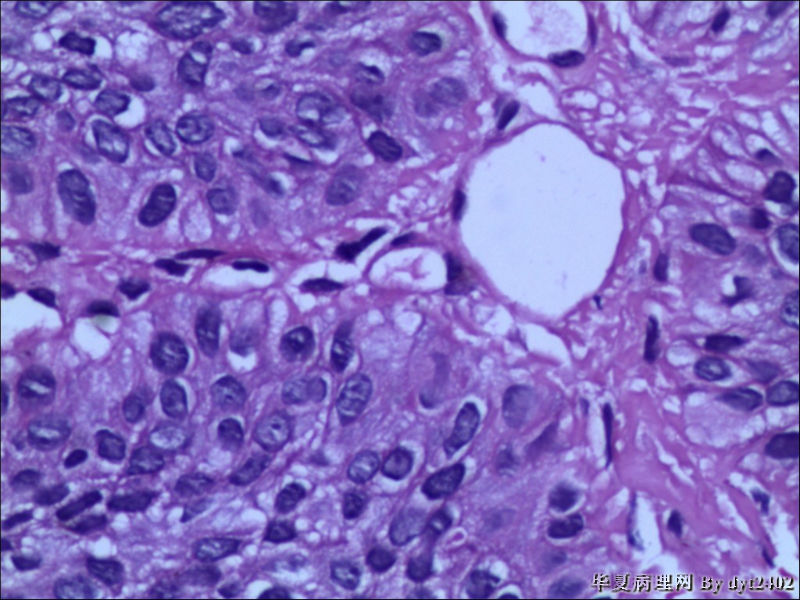

这样的外阴病变 发个原位癌是否合适?

• 这样的外阴病变 发个原位癌是否合适?图3

图3

原位癌够了,不排除其他地方有浸润。

似乎有浸润了

VIN III,做个银染或者标个免疫组化看一下基底膜是否完整。

看上去好像还完整 只是经常看见图5 那样结构的就觉得可能还有更重病变

VIN III